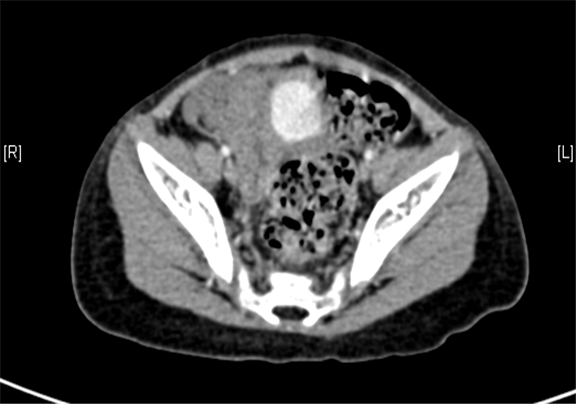

下腹部增强CT示右下腹腔内巨大软组织块影并右肾、输尿管积水。

术前CT检查:

动脉期

静脉期

平衡期